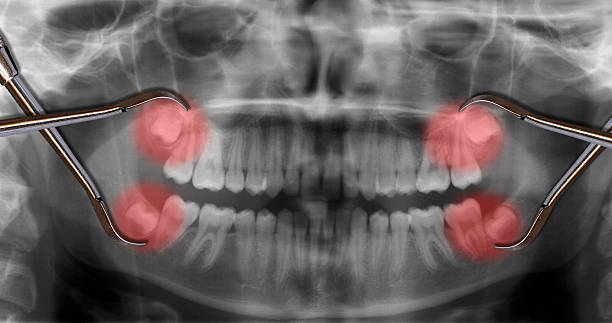

ฟันคุดคือ ฟันกรามซี่ในสุด ทั้งหมด 4 ซี่ บน ล่าง ซ้าย ขวา ไม่สามารถขึ้นได้ตามปกติเพราะพื้นที่ไม่เพียงพอให้ฟันสามารถขึ้นมาได้ บางซี่อาจจะโผล่ขึ้นมาเล็กน้อย และบางซี่ถูกฝั่งอยู่ในกระดูดขากรรไกร อาจจะขึ้นตรง เอียงหรือนอนในแนวราบส่วนใหญ่ฟันคุดมักพบว่าอยู่ที่ฟันกรามซี่ล่างในสุดและพบมากสุดในช่วงอายุ ประมาณ 16 – 25 ปี หรืออาจจะช้ากว่านั้น